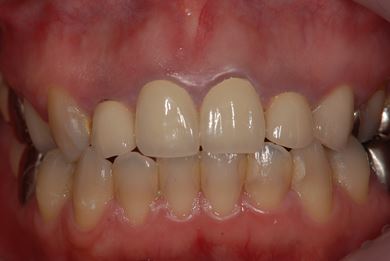

インプラントの症例写真 IMPLANT

インプラント治療

| 性別/年齢 | 女性 / 34歳 | ||||||||||||||||||||||||||||||||

| 治療方針 | 右下奥欠損部分をインプラント治療にて機能的・審美的回復を行う。 | ||||||||||||||||||||||||||||||||

| 治療内容 | インプラント1本、メタルボンドセラミッククラウン1本 | ||||||||||||||||||||||||||||||||

| 総治療費 | 252,000円 | ||||||||||||||||||||||||||||||||

| 治療期間 | 4ヶ月 |